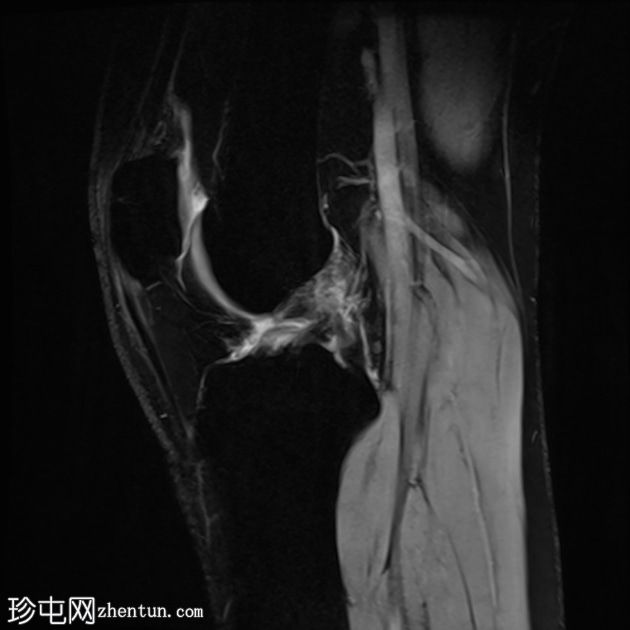

矢状位

T2-ME3D-WE序列

外侧副韧带也存在水肿,纤维断裂,提示为III级损伤。

影像学结果显示外侧副韧带III级损伤(完全撕裂),同时伴有前交叉韧带完全撕裂和骨挫伤。

患者随后接受了关节镜手术,手术证实了诊断,并重建了前交叉韧带和外侧副韧带。